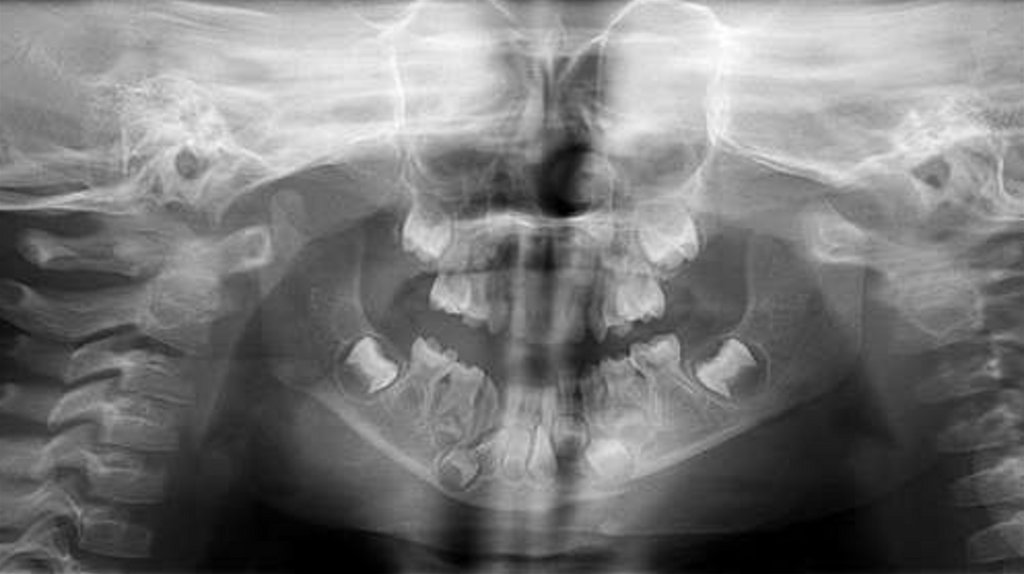

Девятнадцать пациентов в возрасте от 3 до 12 лет с челюстнолицевыми повреждениями были рассмотрены Отделением

Были собраны подробные истории болезни, проведены

клинические и рентгенографические исследования, такие как

ортопантомография, окклюзионная рентгенография и

внутриротовая периапикальная рентгенография . После

тщательной оценки был поставлен диагноз типа перелома и был

составлен план лечения для каждого пациента.

У всех пациентов шины и дуги были удалены через 2-4 недели.

Послеоперационные рентгенограммы были получены для

подтверждения заживления места перелома перед удалением

шины (рис. 5 и рис. 8), и все пациенты наблюдались в течение 12